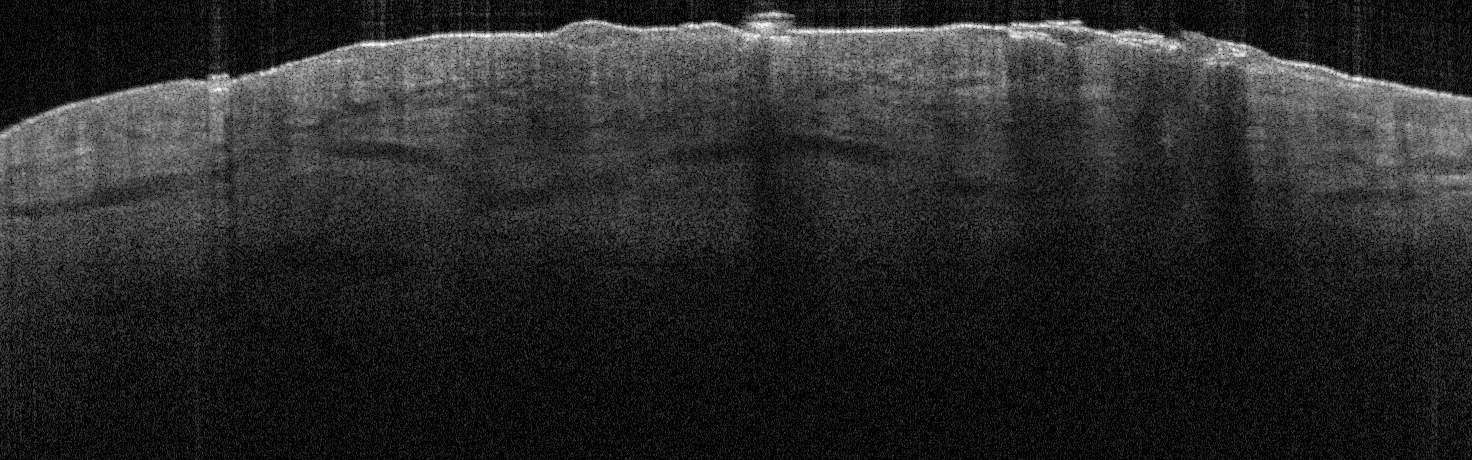

VA35: Left Temple, Adjacent, Normal